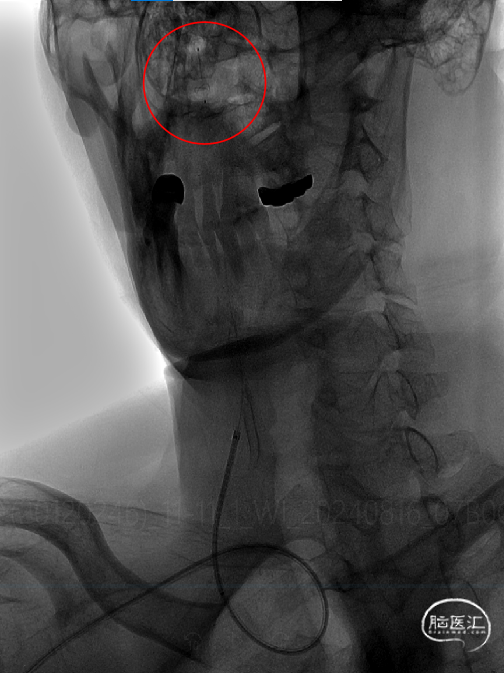

建立通路:

以260cm泥鳅导丝辅助125cm Simmons 2和6F导引导管超选右侧颈总动脉远端,撤出泥鳅导丝及造影管,再次造影可见右侧颈内动脉起始部重度狭窄,狭窄率约80%。